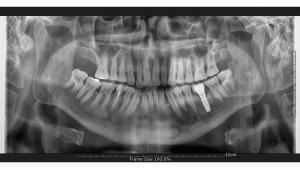

This is because, in some cases, there may be an infection in the teeth that need to be extracted, even if it is minor. By using medication for infection, we ensure that our patients have a more comfortable implant operation and postoperative period.When our patients come to our clinic in Marmaris, Turkey, for a full set of dental implants, we first perform a detailed examination with a panoramic x-ray and oral examination. Based on the examination results, our doctors create a treatment plan. We then proceed with the implant surgery process to provide our patients with the best treatment possible.